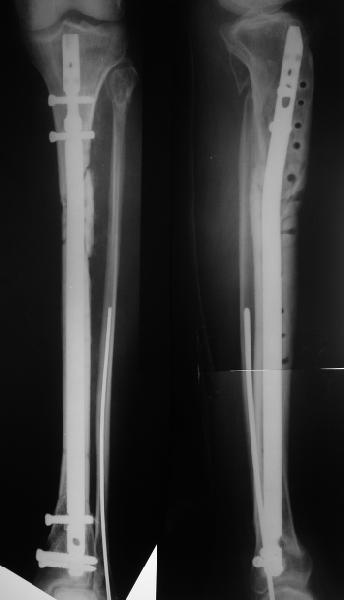

Еще раз спасибо! Сделали вчера. Все прошло по плану, интраоперационное фото после удаления пластинки и итоговые снимки прилагаю. Гвоздь бесканальный 12 мм. Сегодня пациентка уже ходит по палате с одним костылем.